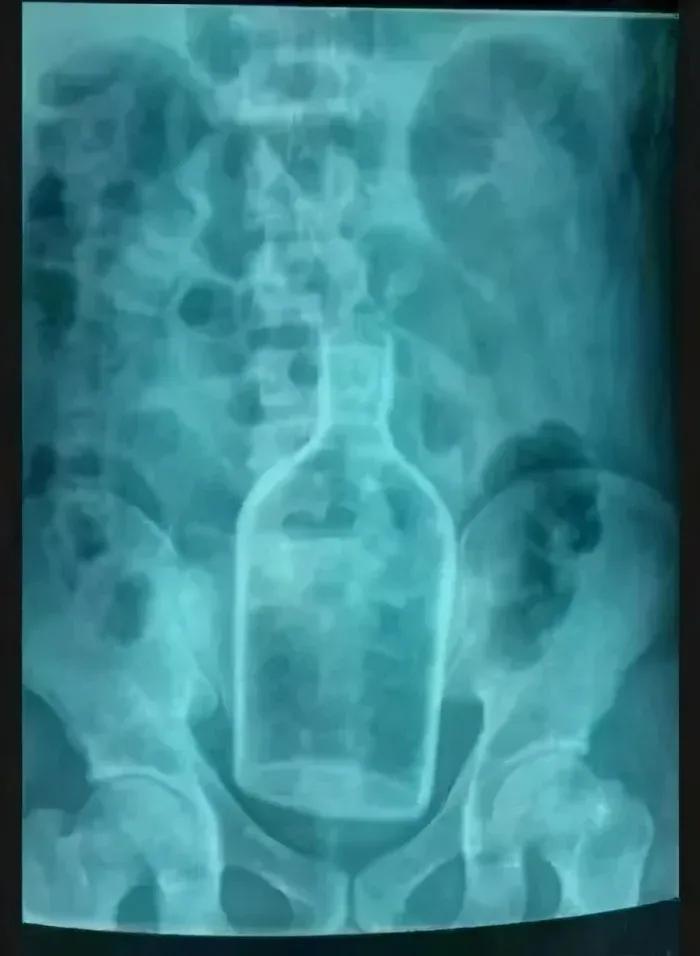

塞进去的东西就比较五花八门了,沐浴露、胡萝卜、鸵鸟蛋、水果刀、啤酒瓶,甚至还有活物……

塞进去的异物就比较难治疗了,一般是先需要医生进行肛门指检,再选择适宜的手术方式。通俗点说,就是手掏大便,看看异物深浅。

像文章开头的那位兄台,就只能进行开腹手术了。虽然不能体验分娩的感觉,但可以体验一次“剖腹产”的痛感。